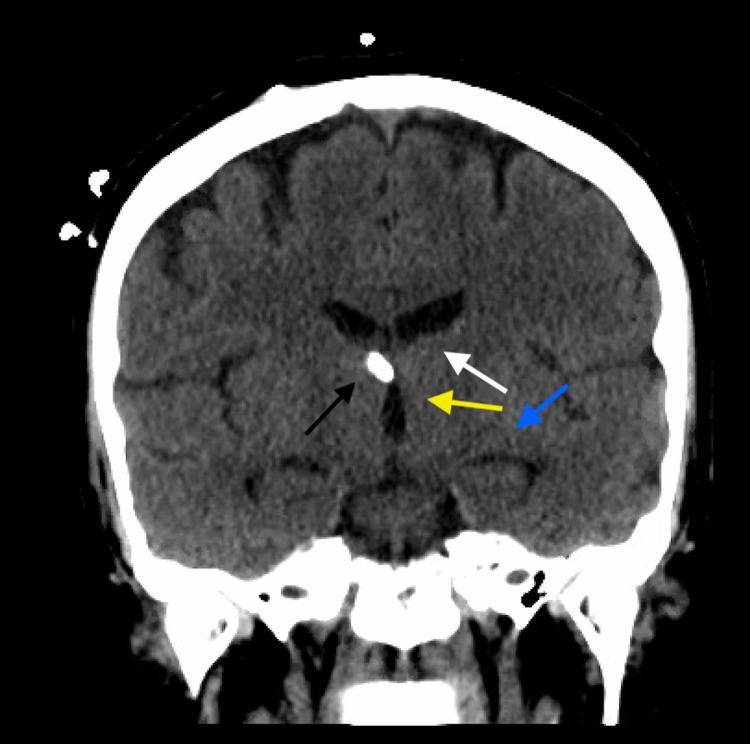

A preliminary report warned that severe acute respiratory syndrome coronavirus 2 (SARS-CoV-2) could have neuro-invasive potential as it was observed that some patients showed neurologic symptoms such as headache, nausea, and vomiting. Following early speculation there have been reports of neurologic manifestations involving both the central nervous system and peripheral nervous system including reports that coronavirus disease 2019 (COVID-19) may increase the risk of acute ischemic stroke. Here we present a patient with recent COVID-19 infection who experienced low-pressure hydrocephalus requiring high-output cerebrospinal fluid (CSF) diversion following spontaneous angiogram-negative subarachnoid hemorrhage. We hypothesize that patients who are either currently or who have recently been infected with SARS-CoV-2 may have altered ventricular compliance and/or altered CSF hydrodynamics from mechanisms that are not yet understood but potentially related to previously described pathophysiologic mechanisms of the virus and associated inflammatory reaction.

一份初步报告警告称,严重急性呼吸综合征冠状病毒2(SARS-CoV-2)可能具有神经侵袭潜力,因为观察到一些患者出现头痛、恶心和呕吐等神经症状。在早期猜测之后,有报道称神经系统表现涉及中枢神经系统和周围神经系统,包括有报道称2019冠状病毒病(COVID-19)可能增加急性缺血性中风的风险。在此,我们报告一名近期感染COVID-19的患者,该患者在自发性血管造影阴性蛛网膜下腔出血后出现低压性脑积水,需要进行高流量脑脊液(CSF)分流。我们推测,目前或近期感染SARS-CoV-2的患者可能存在心室顺应性改变和/或脑脊液流体动力学改变,其机制尚不清楚,但可能与该病毒先前描述的病理生理机制及相关炎症反应有关。